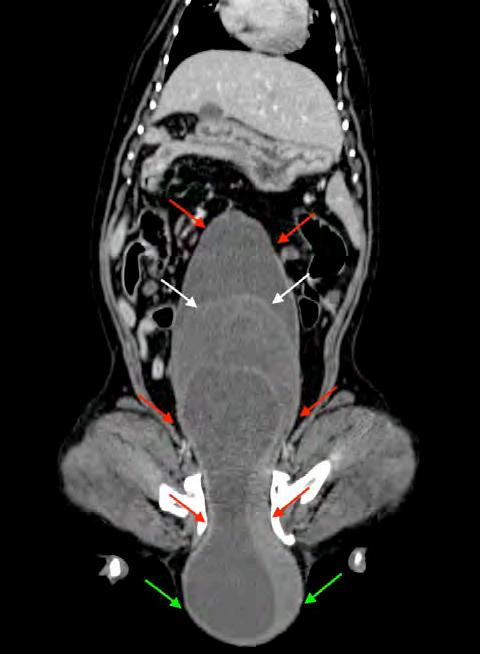

Figura 1. Porcentaje de cepas de Staphylococcus pseudintermedius multirresistentes en función del número de grupos de antibióticos a los que muestran resistencia.

Por otra parte, un 58,8 % (70/119) mostraron características de multirresistencia, considerándose como tal las cepas de SP resistentes a más de tres antibióticos pertenecientes a tres grupos diferentes, con una resistencia media a 5 grupos de antibióticos diferentes (rango 3-7) (Fig. 1). Los aislados que podrían considerarse como “extensive drug resistant” (o, por sus siglas en inglés, XDR, resistentes a 7 grupos de antibióticos diferentes) fueron el 14 % de los aislados MDR (10/70), no observándose ninguna cepa de SP “pandrug resistant” (o PDR, resistente a todos los grupos de antibióticos testados).

El grupo antibiótico al que las cepas aisladas mostraron un mayor porcentaje de resistencia fue el de los macrólidos con un 87 % de muestras resistentes a la eritromicina, seguido de las lincosamidas con un 58 % de resistentes a clindamicina. En el extremo opuesto se situaron los aminoglucósidos con un 21 % de cepas resistentes a la gentamicina y un 1,8 % a la amikacina. La rifampicina mostró un 9 % de aislados resistentes en las 45 muestras en las que se obtuvo este dato (Fig. 2). La resistencia a tetraciclinas y fluoroquinolónicos se situó en un 49 % y 45 %, respectivamente. La resistencia

AFenicoles n=35; *Rifampicina n=45

a los distintos grupos de antibióticos testados.

a sulfamidas fue del 37 % en consonancia con la obtenida para el grupo de los fenicoles, si bien es importante destacar que este último grupo de antibióticos únicamente fue testado sobre 35 muestras (Fig. 2).

Figura 2. Porcentaje de resistencia de los aislados de Staphylococcus pseudintermedius (n=119) frente